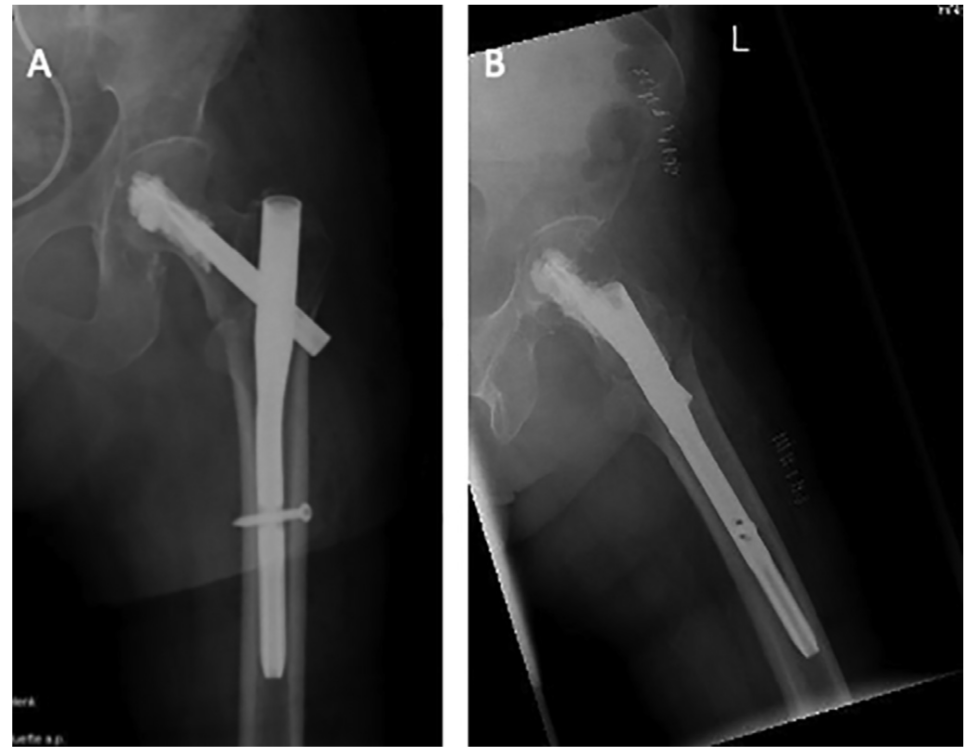

股骨粗隆间骨折PFNA内固定手术技巧,看图就能学会!